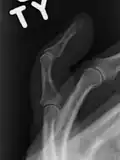

-  			X-ray showing fracture at the insertion of the extensor tendon